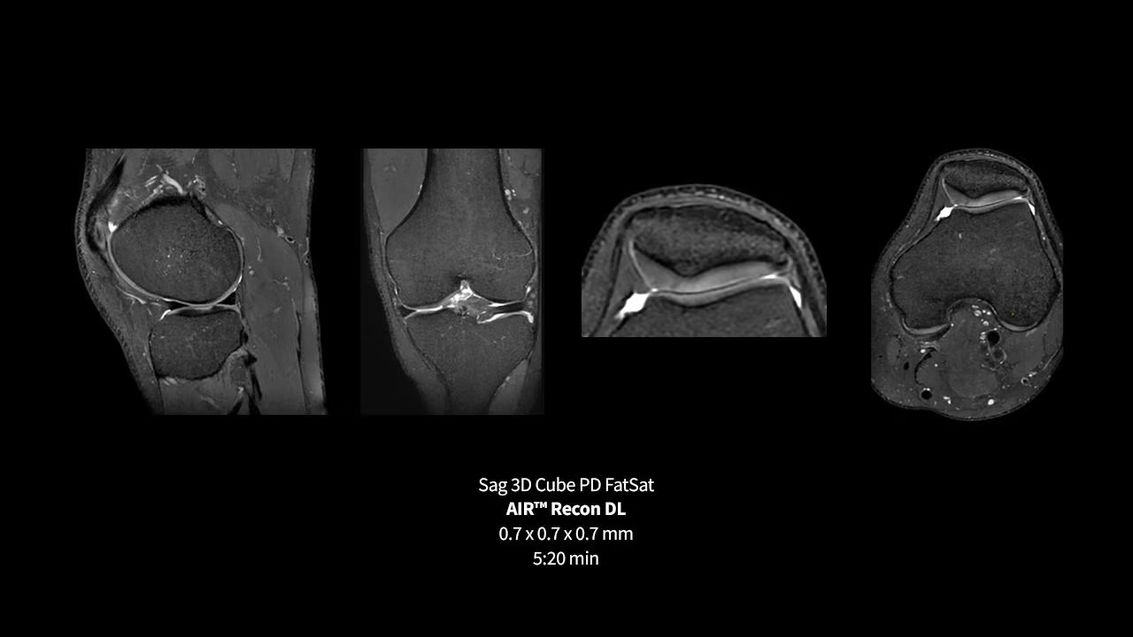

Клинические изображения аппарата МРТ GE SIGNA Premier

GE SIGNA Premier — это аппарат МРТ 3,0 Тесла, который привносит в клиническую практику возможности визуализации исследовательского уровня. Разработанный для расширения границ пространственного и временного разрешения, SIGNA Premier объединяет систему градиента SuperG (до 80 мТл/м при 200 Тл/м/с), массивы катушек AIR для сверхлегкого удобного для пациента сканирования и технологии AIR Recon DL на базе искусственного интеллекта для ускоренного получения данных без ущерба для диагностической целостности.